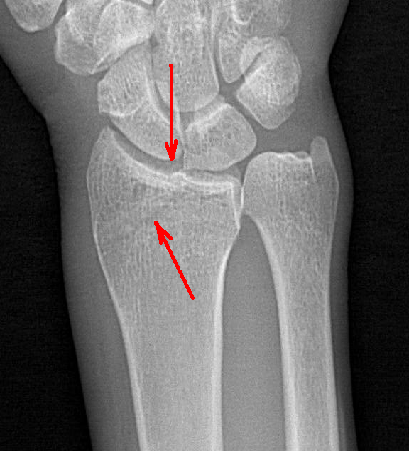

在常規(guī)拍片中,往往由于影像的重疊或體位等因素造成病灶部位漏診,而動(dòng)態(tài)DR具有可視化功能,可以進(jìn)行動(dòng)態(tài)觀察,毫秒級高清點(diǎn)片,更快捕捉到病灶點(diǎn),大大降低漏診誤診幾率。比如,在常規(guī)拍片中易漏診的心臟后病灶、膈肌病變、隱匿肋骨骨折和小兒支氣管異物檢查等,在動(dòng)態(tài)DR攝影中都有很高的確診率。

隱匿性骨折高清圖像